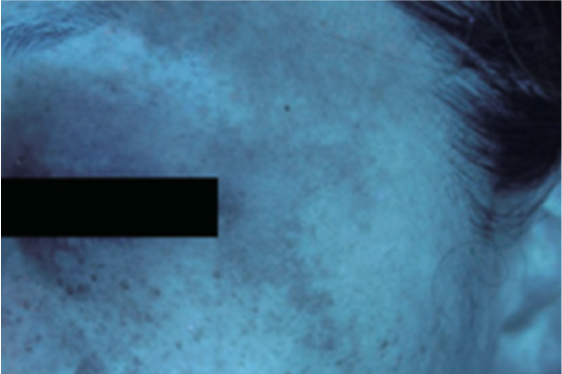

肌画像撮影機

現在の皮膚の状態を可視化します。目視ではわかりにくい隠れたシミや色素脱失を確認できます。

カラー写真

UV写真